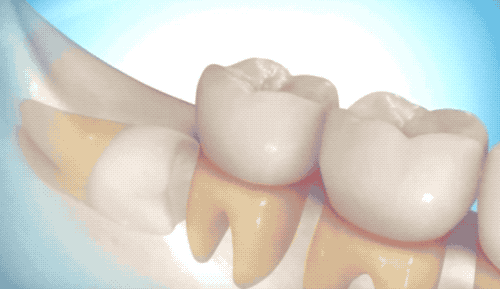

首先介紹相對(duì)簡(jiǎn)單的拔除,雖然沒有完全長(zhǎng)出來(lái),但是沒有長(zhǎng)歪的那類智齒。

切開牙床,翻開牙肉,露出白白的牙槽骨和智齒。很多人白的牙齒可能就是沒有完全萌發(fā)的智齒了…

看到里頭白白的,豎著長(zhǎng)還挺乖的智齒,用牙挺直接撬出來(lái)即可。有時(shí)候醫(yī)生也會(huì)拿錘子敲一敲,用鉗子給揪下來(lái)。